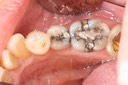

Photos of Clinical Operations

Mentors: Drs. Randy Allan, Greg Card, Peter Kearney

Clubs #44 and #50 joint meeting